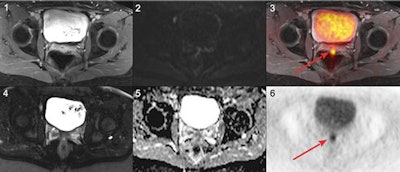

Images are from a 45-year-old woman with local recurrence of endometrial cancer. Postsurgical scar tissue is seen on a T1-weighted fast spin-echo (FSE) volumetric interpolated breath-hold examination (VIBE) (1) and T2-weighted FSE half-Fourier acquisition single-shot turbo spin-echo (HASTE) sequence (4). PET (6) and PET/MR (3) images show a small focus of pathologically increased FDG uptake in the dorsal part of the scar tissue, indicating local relapse. No focal contrast enhancement or tumor was detectable on T1-weighted FSE VIBE (1) and T2-weighted FSE HASTE (4). The local recurrence did not exhibit a clearly focal restricted diffusion on diffusion-weighted MRI (2) and corresponding apparent diffusion coefficient map (5). Images courtesy of Dr. Lino Sawicki.The researchers used patients' histopathology data for reference standards. If histopathology results were not available, the researchers depended on follow-up imaging with a mean interval of eight months, a same-day PET/CT scan, and clinical follow-up.